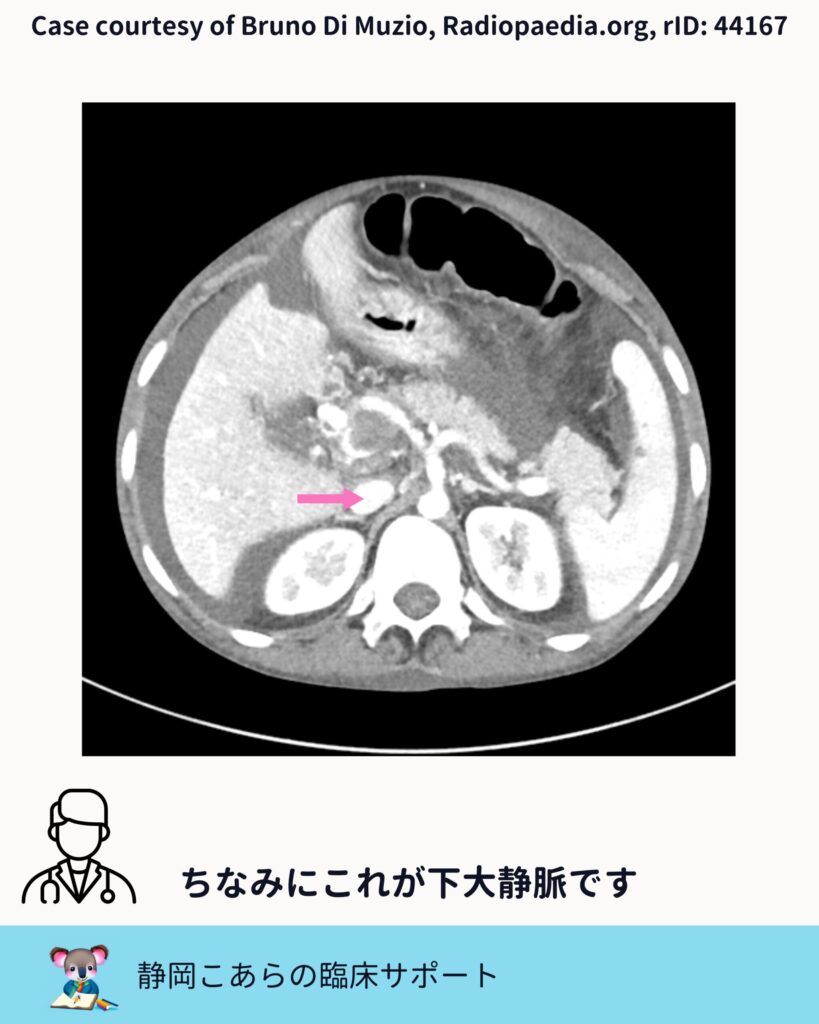

ちなみに下大静脈

比較対象として、下大静脈も確認しておきます。位置関係と造影のされ方を見比べることで、門脈系との違いがより明確になります。

「似ている構造を並べて見る」。これは画像診断全般に通じる、地味ですが効く視点です。